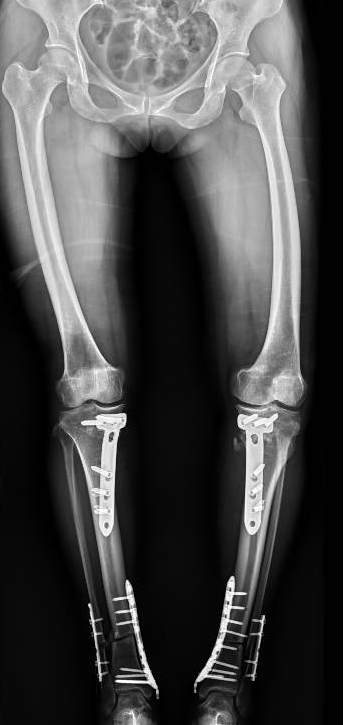

面對這樣復(fù)雜且嚴(yán)重的病情,李彬并沒有退縮。他深知,對于董阿姨來說,這不僅僅是一次手術(shù),更是一次重生的機(jī)會。因此,他精心制定了手術(shù)方案:對雙下肢脛骨近端、遠(yuǎn)端以及雙側(cè)腓骨遠(yuǎn)端進(jìn)行截骨矯形,并進(jìn)行植骨內(nèi)固定。這樣的手術(shù)方案,無疑是對醫(yī)生技術(shù)的一次高難度挑戰(zhàn)!

手術(shù)前 手術(shù)后